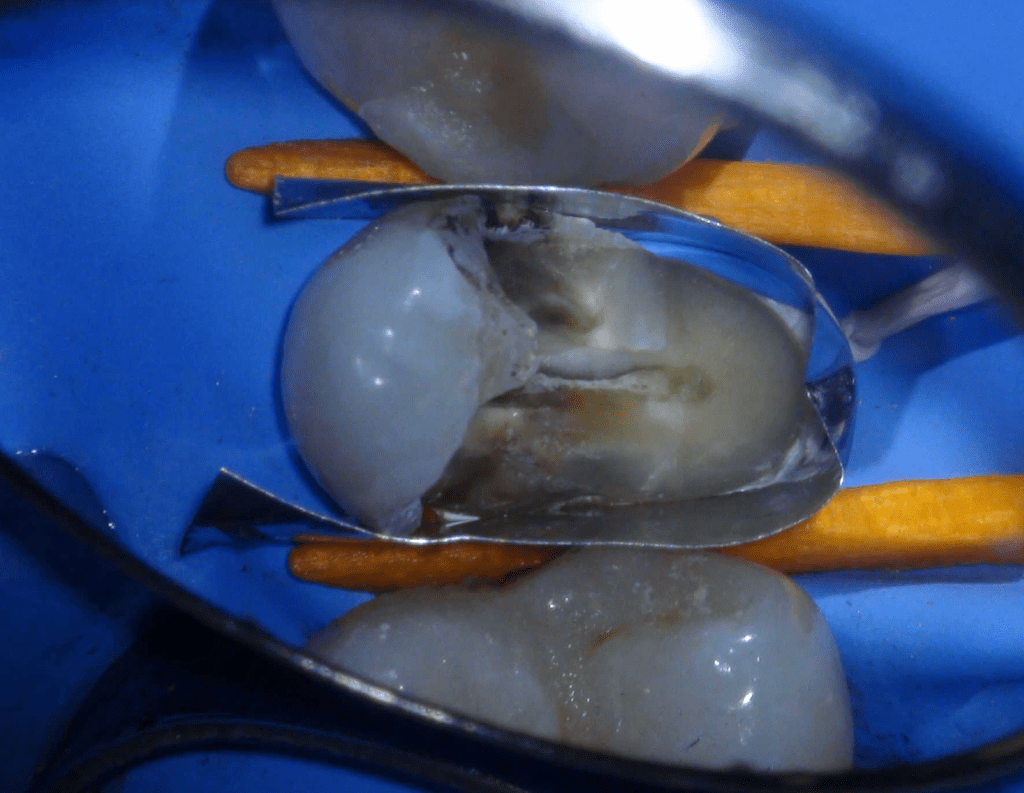

Pulpotomía biodentine + reco preendio